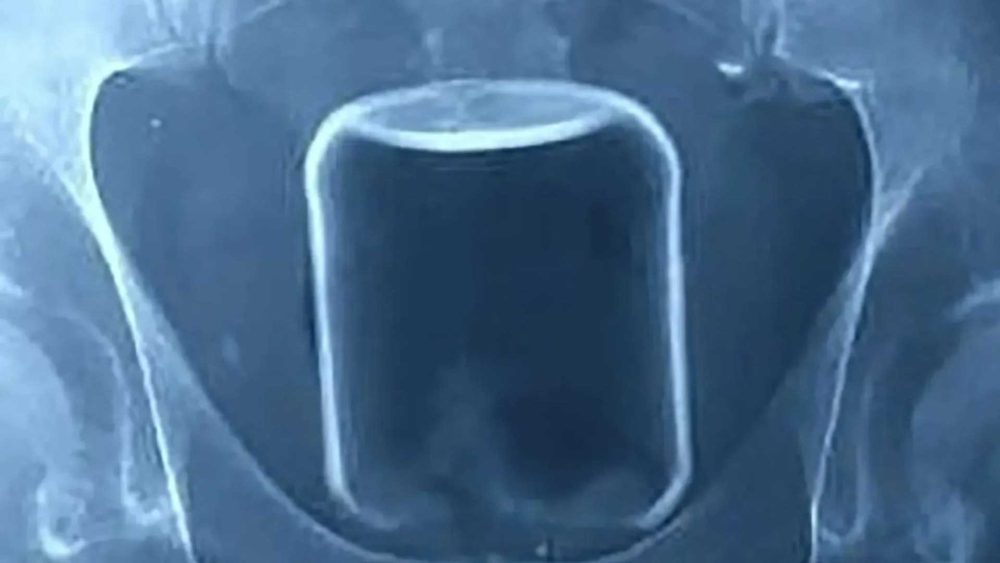

Read moreDetailsA DAD-OF-TWO was left in agony and nearly paralysed in a health scare he mistook for old age that turned out to be cancer. Simon Cummings, 53, was rushed to...